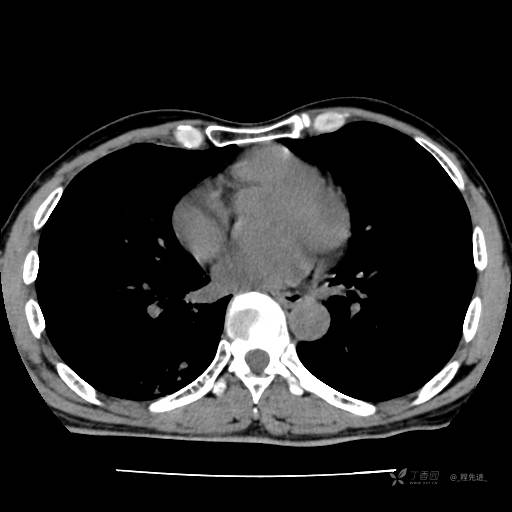

2月特别精彩病例|咳嗽、咳痰20余天,典型病例分享【结果已公布】

患者年龄:51岁

主诉:咳嗽、咳痰20余天

简要病史:20余天前开始出现咳嗽、咳痰症状,阵发性刺激性咳,白色粘痰,不易咳出,无发热,无咯血,无恶心、呕吐等不适,未诊治,咳嗽、咳痰症状持续存在。

体格检查:T:36.3 ℃ P:79 次/分 R:20 次/分 BP:128/64 mmHg,神志清楚,呼吸平稳,双肺呼吸音粗,右下肺闻及细湿性啰音。心率79次/分,节律整齐,各瓣膜听诊区未闻及病理性杂音。腹部未见异常,双下肢无水肿。

辅助检查:我院门诊胸部CT示:如下。心电图:窦性心律;正常心电图。